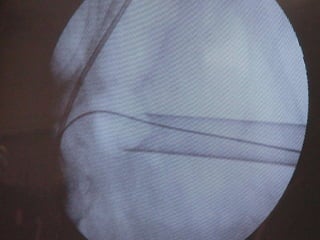

O documento discute o tratamento de urolitíase, especificamente a remoção de cálculos renais através de nefrolitotripsia. A cirurgia aberta é agora muito restrita devido aos avanços da ESWL e procedimentos endourológicos menos invasivos como ureteroscopia e cirurgia percutânea. A cirurgia laparoscópica está substituindo a cirurgia aberta como técnica menos invasiva que combina a tecnologia endourológica com a laparoscópica preservando